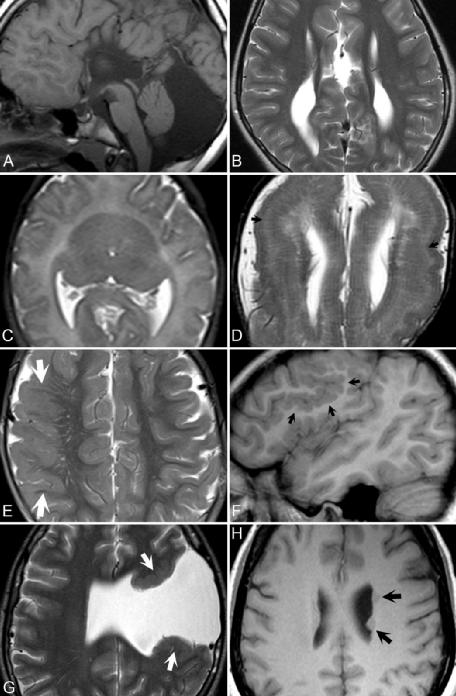

胼胝体畸形以完全或部分形式出现。胼胝体的形成是从前到后进行的,因此在部分发育不全中,前部通常得到保留,如图25.1 A所示(尽管在这种情况下,仅存在一小部分胼胝体)。注意延伸至脑室边缘的特征性放射状脑沟模式。在胼胝体难以观察的新生儿中,放射状脑回可能是发育不全的诊断重要信息。图中可以看的巨大枕大池(图25.1 A)、Chiari 2型畸形和Dandy-Walker畸形伴胼胝体发育不全。平行的侧脑室(图25.1 B)是特征性的,在冠状位图像上,由于(Probst的)白质束沿其中侧壁分布,侧脑室可能呈新月形。

前脑无裂畸形是一种前脑(前脑)不能发育为两个半球的先天性畸形。本文展示了脑叶型、半脑叶型和无脑叶型,其程度从轻度到重度不等。无脑叶型(最严重)缺乏第三脑室、大脑镰和半球间裂。融合或缺失的丘脑以及马蹄形单脑室是特征性表现。图25.1 C显示了一例半脑叶型病例,其中半球间裂在前方明显缺失(尽管在后方存在),丘脑大部分融合。单脑室分为后角而不是前角。脑叶型最不严重,其特征为无透明隔,少量额叶融合(下方),丘脑、脑室和胼胝体几乎正常。

无脑回畸形是指厚脑回和无脑回中所见的“光滑大脑”的大体MRI表现。图25.1 D显示了后者中可见的初级脑回形成。细胞稀疏区(黑色箭头)-主要由轴突组成-在T2WI上可视为一个高信号区,位于薄的低信号皮质(代表成功迁移的神经元)和灰质深层(神经元迁移已被中断)之间。在图25.1 E中,在局灶性厚脑回病例中,平滑、增厚的灰质(白色箭头)衬于脑回表面。本病例中的脑沟较浅,但比无脑回更突出。多脑回畸形可能看起来与巨脑回大体相似,但病理上皮质脑回太小太多。灰质分叶状,称为鹅卵石样变(图25.1 F,黑色箭头),是MRI的一个特征性发现。其位置(累及大脑)和外观多种多样。

脑裂畸形是一种迁移性疾病,会导致大脑半球从皮质到脑室出现裂缝。图25.1 G显示了一个开放脑裂畸形病例,脑室和蛛网膜下腔之间有广泛的交通。裂隙旁的灰质(白色箭头)将异常定义为脑裂畸形,而不是脑穿通畸形或其他破坏性病变。

▲ 图25.1

灰质异位由脑室和脑表面之间的双层皮质组成。在另一名患者中,图25.1 H(黑色箭头)显示了两个异位灰质区域最常见的位置—排列在侧脑室周围。此类病灶在所有序列上均表现出与灰质等强度,但不强化,最好在重T1WI上鉴别,其中灰质和白质的鉴别更好。视隔发育不良(暂无图)是值得注意的最后一种先天性畸形,可导致失明、癫痫、下丘脑-垂体功能障碍和生长迟缓。透明隔发育不良或缺失,存在视神经发育不全。